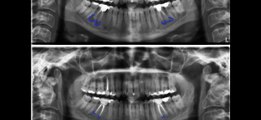

wsr ist die abkürzung für wurzelspitzenresektion. ein chirurgischer eingriff, der in der regel nichts bringt https://www.youtube.com/channel/UCtfezrProo8WbGBSwaEOMIA/search?query=wsr